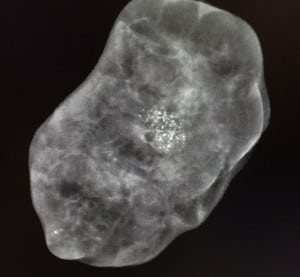

Caso 3.

Imágenes de biopsia de mínima invasión percutánea (a través de la piel en una incisión menor a 1cm)